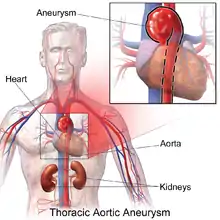

A thoracic aortic aneurysm is an aortic aneurysm that presents primarily in the thorax.

A thoracic aortic aneurysm is the "ballooning" of the upper aspect of the aorta, above the diaphragm. Untreated or unrecognized they can be fatal due to dissection or "popping" of the aneurysm leading to nearly instant death. Thoracic aneurysms are less common than an abdominal aortic aneurysm.[2] However, a syphilitic aneurysm is more likely to be a thoracic aortic aneurysm than an abdominal aortic aneurysm. This condition is commonly treated via a specialized multidisciplinary approach with both vascular surgeons and cardiac surgeons.